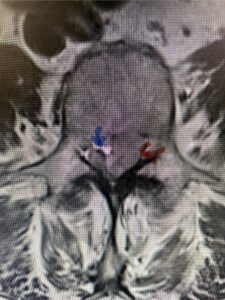

The next patient is a 56-year-old morbidly obese female who had progressive leg pain and weakness. She was over 320 lbs and did not have diabetes either. On MRI she had a massive disc herniation spanning the L3-4 and L-4 interspaces, centered behind the L4 vertebral body (Fig 3A and B). She also had an L4-5 spondylolisthesis. There were opinions that the disc emanated from the L3-4 disc space, but because of spondylolisthesis and on careful inspection of the MRI, there was a high chance the disc herniation had instead emanated from L4-5 (Fig 4). She had conservative treatment including epidurals but had worsening strength and numbness. She was scheduled electively for surgery, but then fell, and broke her ankle. She could not walk, particularly due to the pain down her leg. She was taken to the operating room urgently after she was cleared medically. She had no issues cardiologically and was taken to the operating room. The patient underwent a laminectomy that extended above the L3-4 disc space to below the L4-5 disc space. We encountered mainly centered on the left at the level of the L4 vertebral body and massive disc herniation that created a huge cavity in the lumbar canal. It was covered in an interesting thin membrane that we dissected off the disc herniation (Fig 5). Postoperatively the patient did experience significant relief of pain, but some improvement of strength. In combination with the ankle fracture and the extent of preoperative weakness, the patient required extensive rehab. The patient also developed a seroma and some wound drainage issues that were treated locally.

Fig. 3a : Sagittal T2-weighted lumbar MRI demonstrating a massive L4-5 disc herniation with superior migration behind the L4 vertebral body and taking up most of the left side of the spinal canal (red arrow) Note the slight grade one spondylothesis at L4-5 (blue dash). Notice the severe compression of the thecal sac (blue arrow) by the large left sided disc herniation (red arrow)